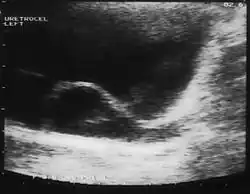

Ureterocele

A ureterocele is a congenital abnormality found in the ureter. In this condition the distal ureter balloons at its opening into the bladder, forming a sac-like pouch. It is most often associated with a duplicated collection system, where two ureters drain their respective kidney instead of one. Simple ureterocele, where the condition involves only a single ureter, represents only twenty percent of cases.

Since the advent of the ultrasound, most ureteroceles are diagnosed prenatally. The pediatric and adult conditions are often found incidentally, i.e., through diagnostic imaging performed for unrelated reasons.